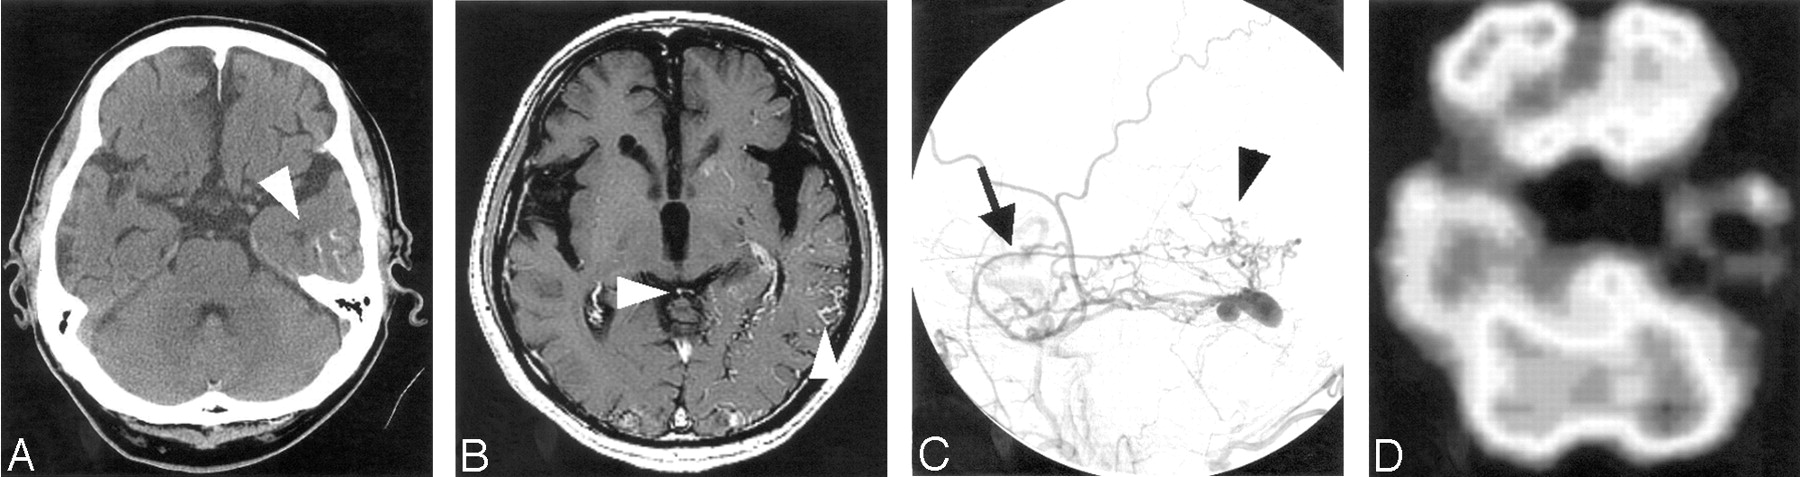

Case 3.

A, CT scans shows diffuse atrophy and subtle calcification in the basal ganglia and subcortical region at the bottom of cerebral gyri bilaterally. The subcortical calcification was curvilinear and predominant on the right side.

B–E, Right external carotid angiograms (B–D, lateral projection; E, frontal projection) show dAVF fed by the enlarged middle meningeal (arrow) and ascending pharyngeal arteries with cortical venous reflux (arrowheads).

F, Repeated CT scans after 1 year reveal a more advanced degree of diffuse atrophy and denser subcortical calcification.

By means of transvenous embolization, arteriovenous shunt was partially resolved with partial disappearance of CVR, and her symptom of convulsion became controllable. Approximately 1 year after the initial embolization, she developed uncontrollable convulsion again, and repeat CT showed advanced degree of diffuse atrophy and denser subcortical calcification. She underwent transarterial re-embolization immediately followed by surgical isolation of the right transverse sinus and remains free of convulsion.